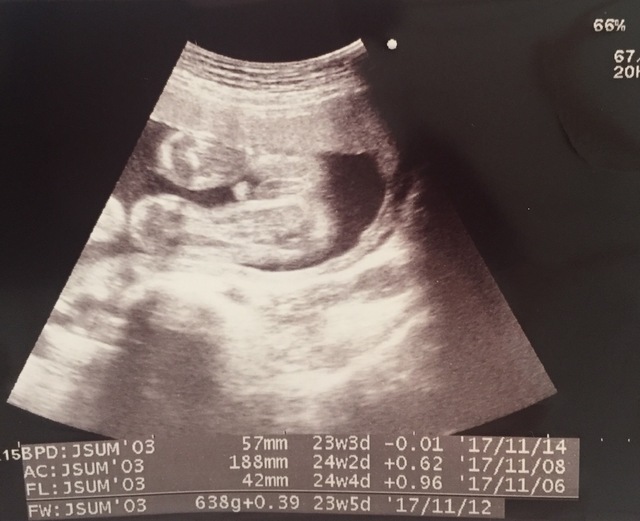

23週5日(23w5d・男の子)|とみとみ さん(29歳)

エコー写真撮影時のエピソード:

初めてエコー写真を見た時、このマメのようなものが人間になるの?と不思議な気持ちになりました。主人もこれ?と実感がわかない様子でしたが、月日が経つにつれて人間らしい姿になってくことに感動!

家族にも毎回エコー写真を送り成長を見てもらっていますが、すごーい、神秘だよねと毎回みんなで感動しています。